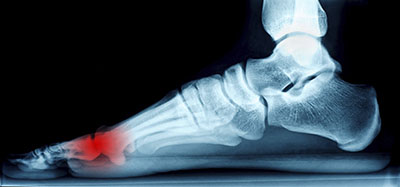

Morton's Neuroma, also called Intermetatarsal Neuroma or Plantar Neuroma, is a condition that affects the nerves of the feet, usually the area between the third and fourth toe. Neuroma refers to a benign growth that can occur in different parts of the body. Morton's Neuroma strictly affects the feet. This condition causes the tissue around the nerves that lead to the toes to become thick, causing pain in the ball of the foot.

This condition can be caused by injury, pressure or irritation. Normally no lump will be felt, but instead burning pain in the ball of the foot that will often be sensationalized in the toes will be experienced. Numbness and tingling may also occur. With the onset of this condition, a person may feel pain when tight or narrow shoes are worn. As the condition worsens, the pain may persist for days, or even weeks.